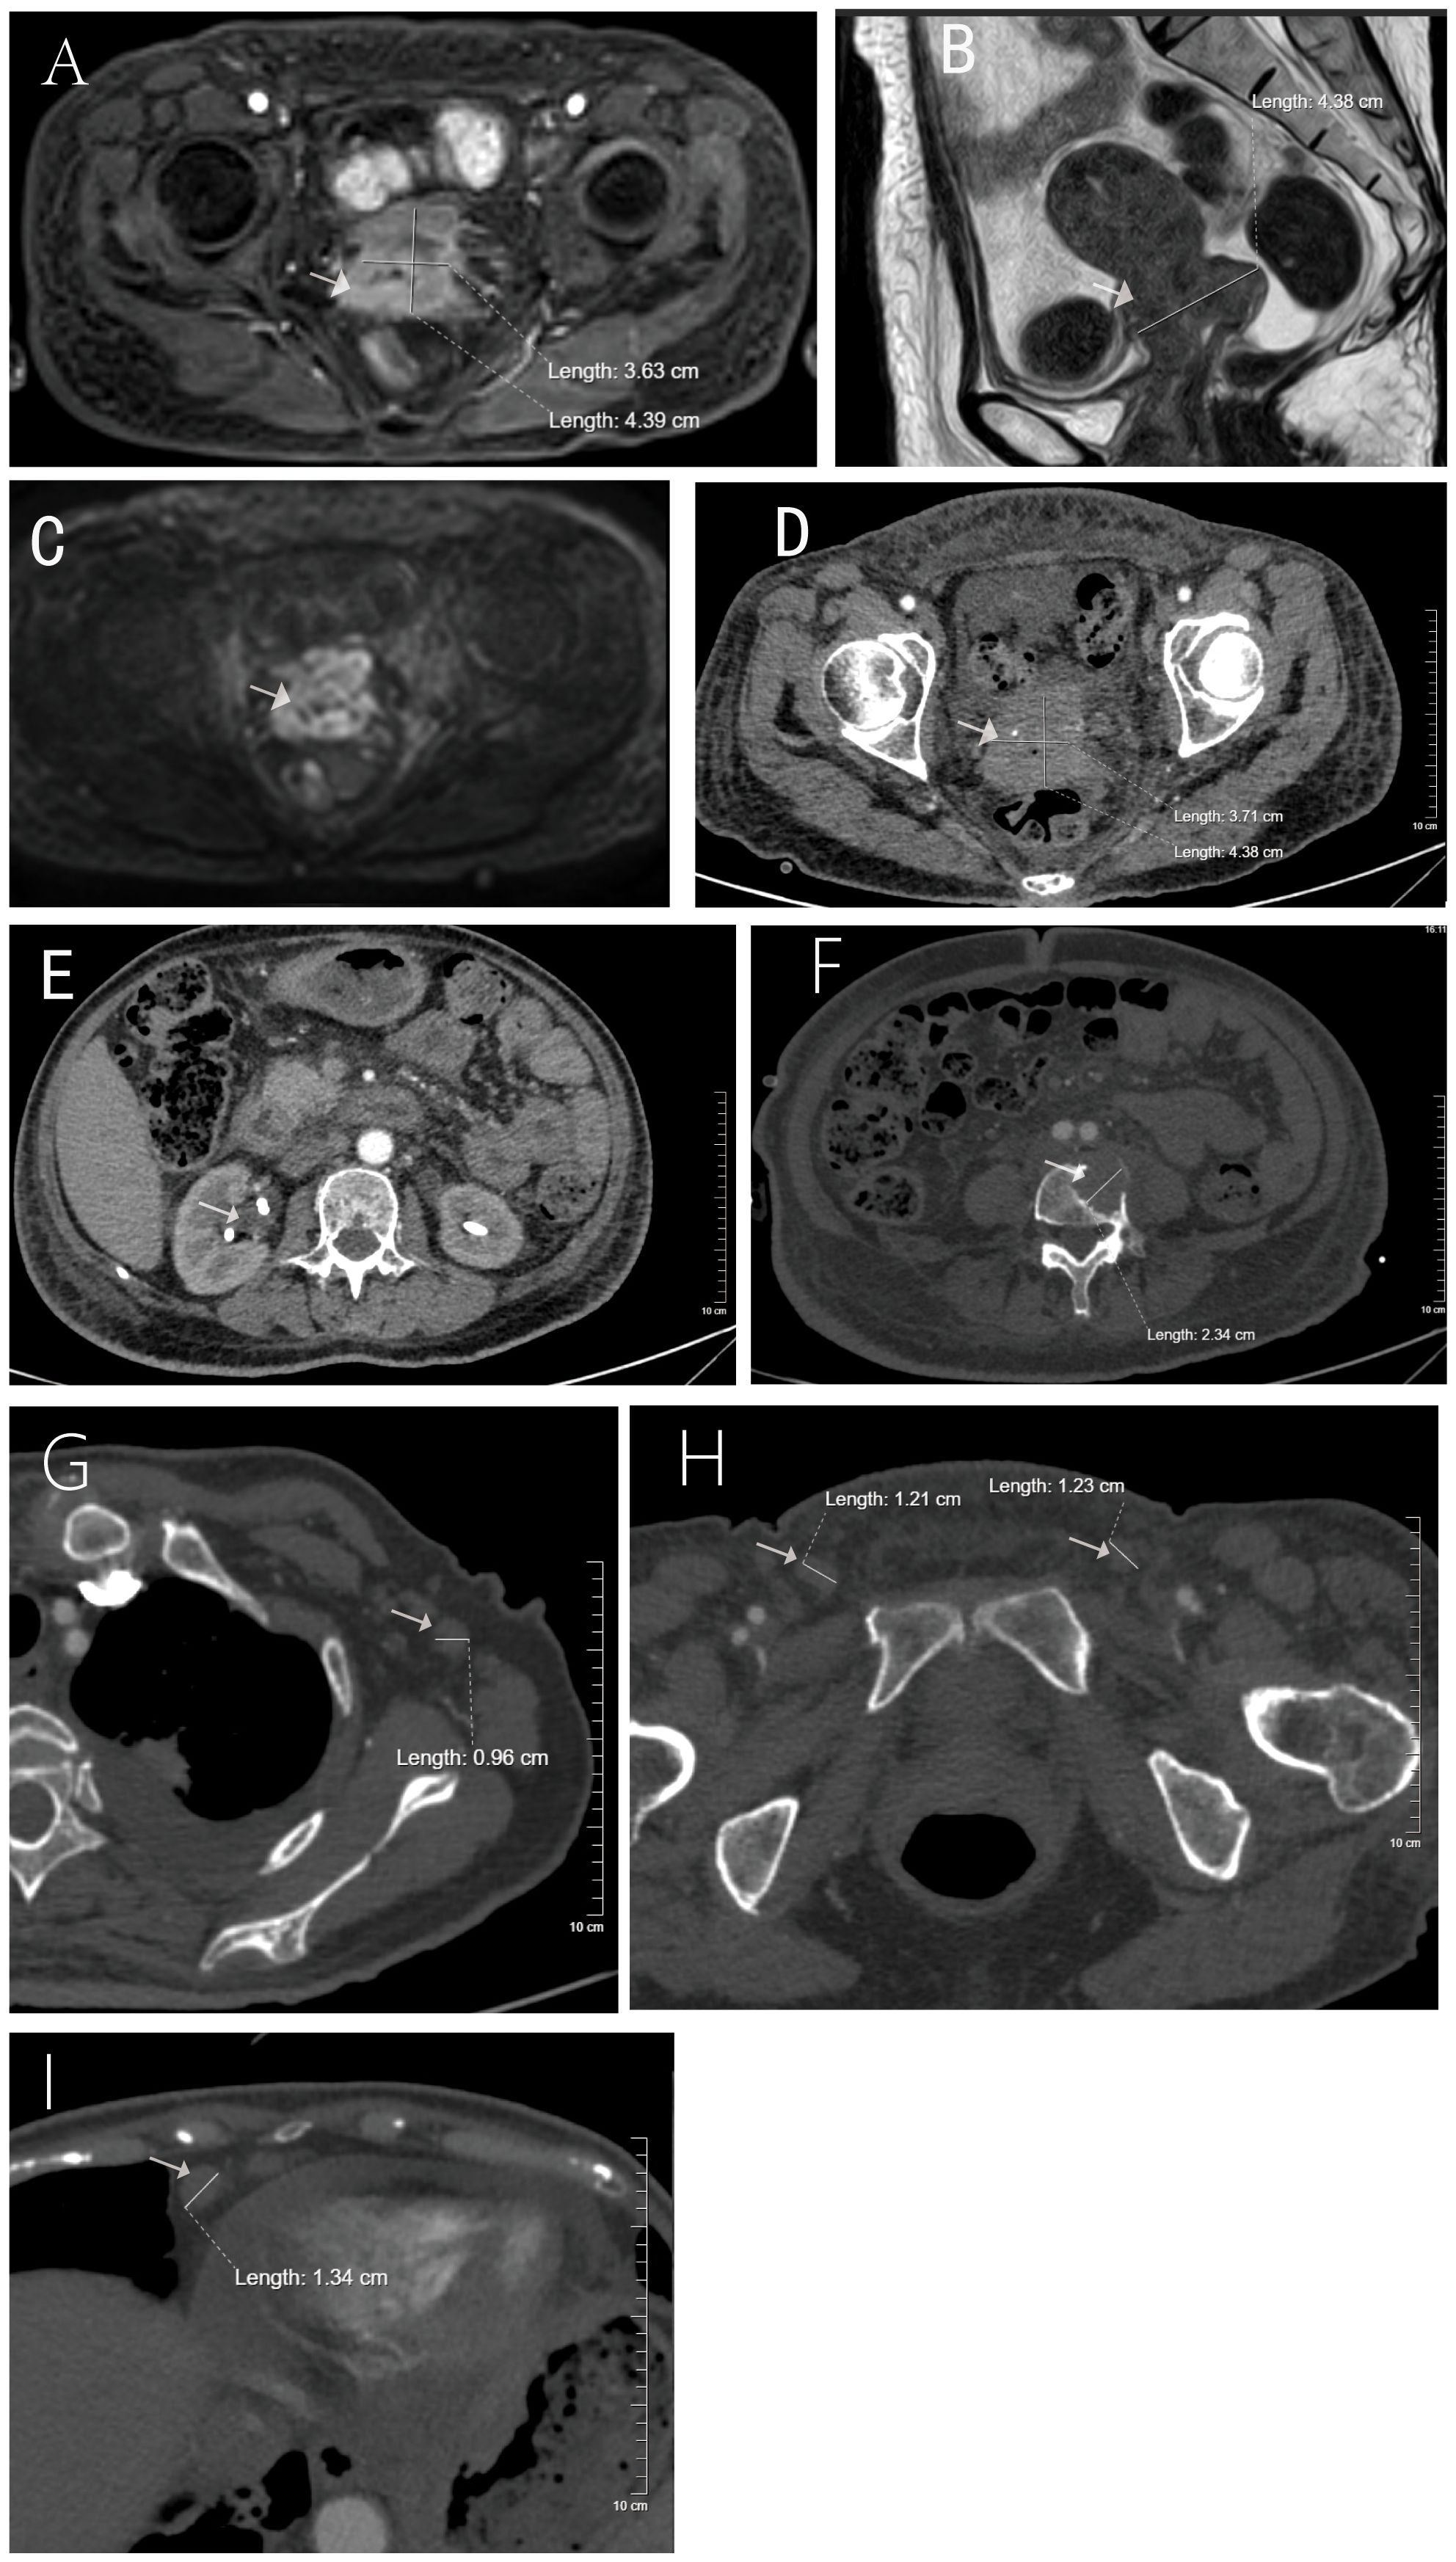

We present a 55-year-old non-obese female exhibiting rapidly progressive malignant acanthosis nigricans (MAN) as the initial manifestation, characterized by widespread malodorous skin lesions preceding the ultimate diagnosis of human papillomavirus 16 (HPV16)-positive poorly differentiated cervical squamous cell carcinoma by four years. Following chemotherapy, both tumor markers and cutaneous manifestations demonstrated rapid regression. However, at the most recent follow-up (August 2025), the patient was hospitalized for management of grade 3 myelosuppression and a secondary pulmonary infection, requiring a temporary suspension of antitumor therapy. This treatment-response correlation provides compelling clinical substantiation for the "tumor-secretory factor-driven" pathogenesis, indicating that MAN may serve as a critical early paraneoplastic signal of HPV-associated gynecologic malignancies and warranting prompt systemic screening upon its recognition.